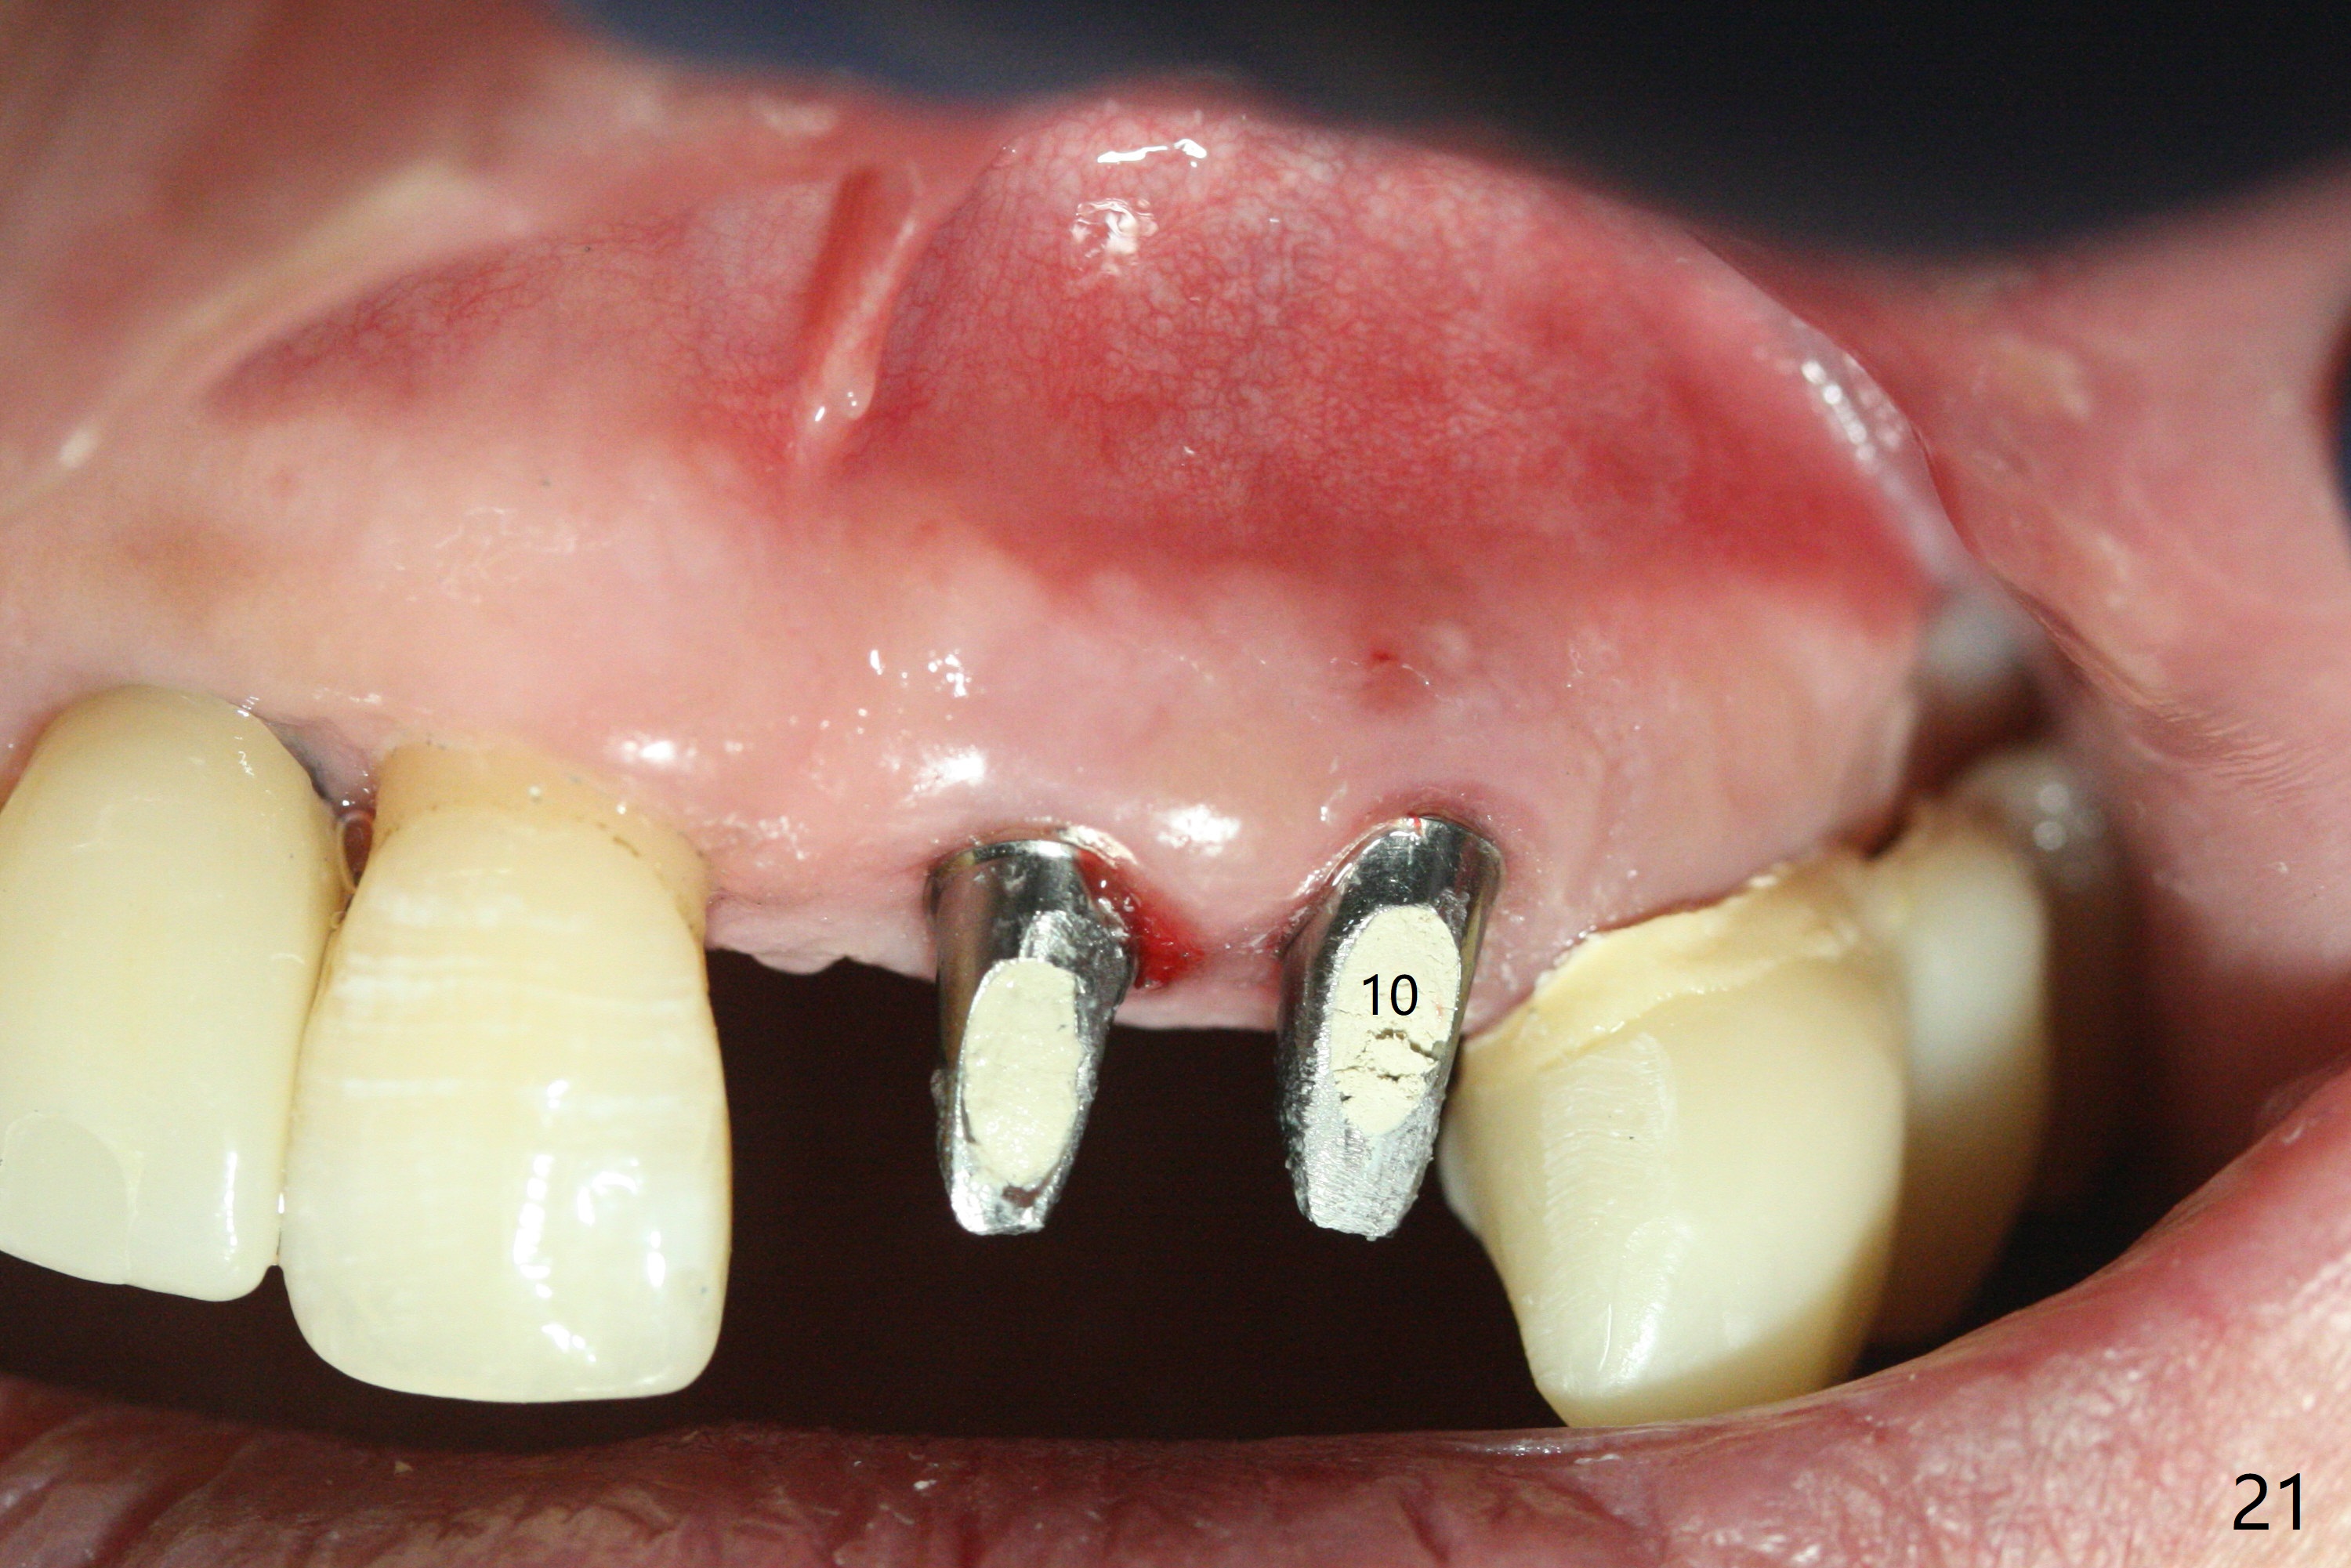

The dentition is poor except #6 and 8 (Fig.1). The gingiva is erythematous at #9-11 (Fig.2). The teeth #9 and 10 are extracted first; a 4x16 mm UF implant is placed at #9, while a 2 mm pilot drill is at the site of #10 (Fig.3). The implant at #9 is placed deeper with placement of 4.5x5.5(5) mm abutment; a 3.8x15 mm implant is placed at #10 initially (Fig.4). While the latter is placed deeper, a 4x16 mm implant is placed at #11 (Fig.5 after removal of #11-15 FPD (fixed partial denture)). In fact the trajectory at #11 is not difficult to be changed with 2 mm drill (Fig.6). After use of 3 mm drill, the implant is reinserted at #11 with ideal trajectory (Fig.7). After further seating of the implant at #11, graft is placed in the remaining sockets of #9-11 (Fig.8 *; later more graft is placed mesial to #11 implant (^)). Finally, a 4.5x7(5), 4.5x15° B (4) and 5.5x7(5) mm abutments are tightened and prepared (Fig.9) for splinted provisional at #9-10.

The patient returns 8 days postop, uncomfortable with overhang in the provisional (Fig.10 *). The sockets appear to be healing with loose bone graft (Fig.11) when the provisional is removed for trimming (Fig.12). Six (for #7,13) and seven (#9-11,15) months postop, the soft (Fig.13,17) and hard (Fig.14-16,18) tissues heal. It appears that the trajectory at #9,11 and 13 should be changed by using angled abutments (Fig.18,19 (panoramic X-ray taken 2 months earlier)) before provisional and final restoration.

There is 1-2 thread exposure mesial and distal at #10 two years postop (Fig.20'), which may be related to the small fistula labially (Fig.20 >). It appears that the implant at #10 was placed too high (Fig.21) and labially (Fig.22). In fact the bridge fractures between #12 and 13 during pandemic.